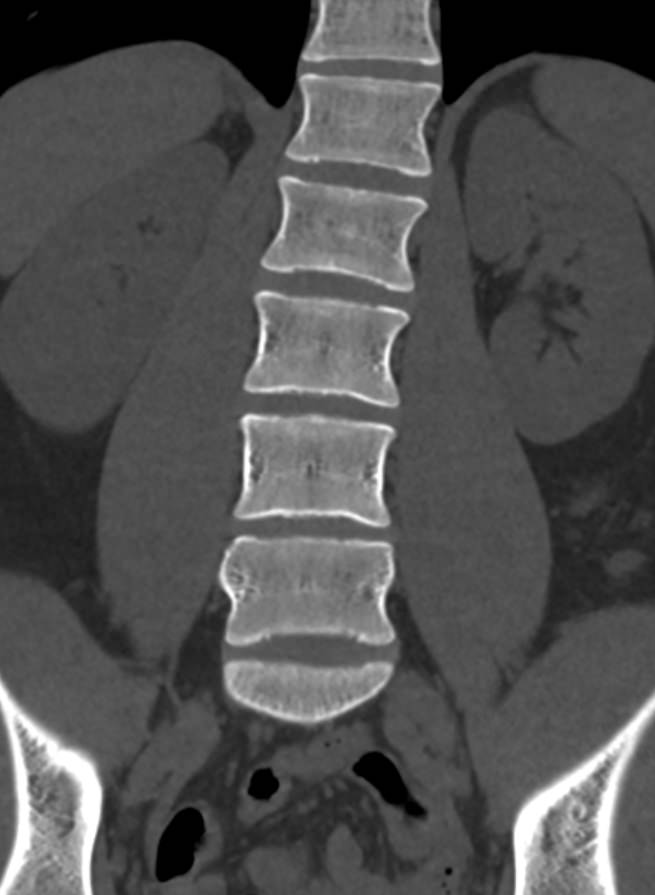

Для диагностики даже незначительных патологических изменений в различных отделах позвоночника, особенно в случае распространенного поражения, применяется один из современных наиболее информативных методов обследования – мультиспиральная компьютерная томография всего позвоночника. Методика основана на использовании проникающей способности рентгеновских лучей через органы и ткани человека и позволяет получить подробное изображение всех структур позвоночного столба. В комплексное обследование входит исследование шейного, грудного, пояснично-крестцового отделов позвоночника и копчика.

В медицинских центрах «Доступная медицина» сканирование всего позвоночника выполняется на новейших мультиспиральных компьютерных томографах последнего поколения TOSHIBA AQUILION в различных модификациях. Особенностью данных аппаратов является их способность проводить от 64 до 128 тончайших срезов одномоментно с минимальной толщиной от 0,5 мм.

Увеличенное количество высокочувствительных детекторов, которыми оснащены томографы, позволяет получать послойные снимки высокого качества с большой скоростью. Эта особенность данных аппаратов обеспечивает быстроту выполнения сканирования. При этом пациент получает минимальную дозу облучения, что имеет важное значение, особенно при такой обширной зоне исследования, как позвоночный столб.